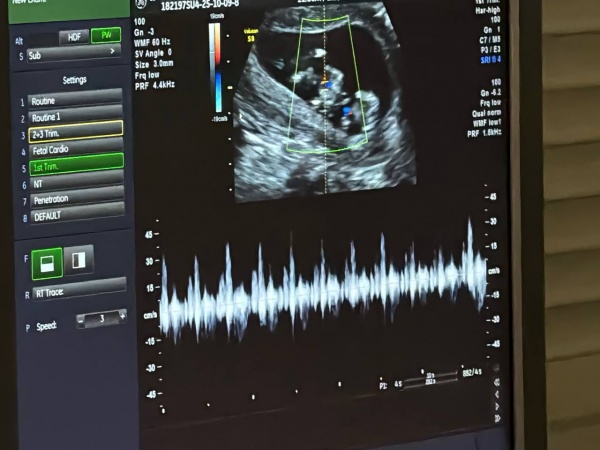

Ведущая медицинская организация по пренатальной диагностике в Костромской области - центр охраны здоровья семьи и репродукции. Здесь в подразделении родильного дома для будущих мам со всего региона создана возможность полного бесплатного обследования. Это позволяет определить возможные риски, чтобы как можно раньше начать лечение. Первый скрининг медики проводят уже на сроке 11-13 недель.

Сергей Ситников вместе с будущими родителями послушал, как бьются маленькие сердца малышей. Врачи считают, что велика вероятность, что двойняшки будут однополыми.

Охват беременных жительниц Костромской области скрининговыми исследованиями ежегодно растет, на данный момент проводится уже более 6 тысяч обследований. Комплекс мероприятий в первом триместре беременности включает биохимический анализ крови на маркеры хромосомных аномалий и комплексную оценку здоровья мамы, пояснила главврач роддома Анна Федоренко. Исследование проводится в специальной медико-генетической лаборатории.

«У нас есть необходимое оборудование. Анализатор проводит биохимию основных показателей. После результаты вместе с результатами УЗИ загружаются в специальную программу, которая рассчитывает возможные риски. Это позволяет своевременно профилактировать осложнения и снизить инвалидизацию деток», - пояснила биолог Юлия Замбржицкая.